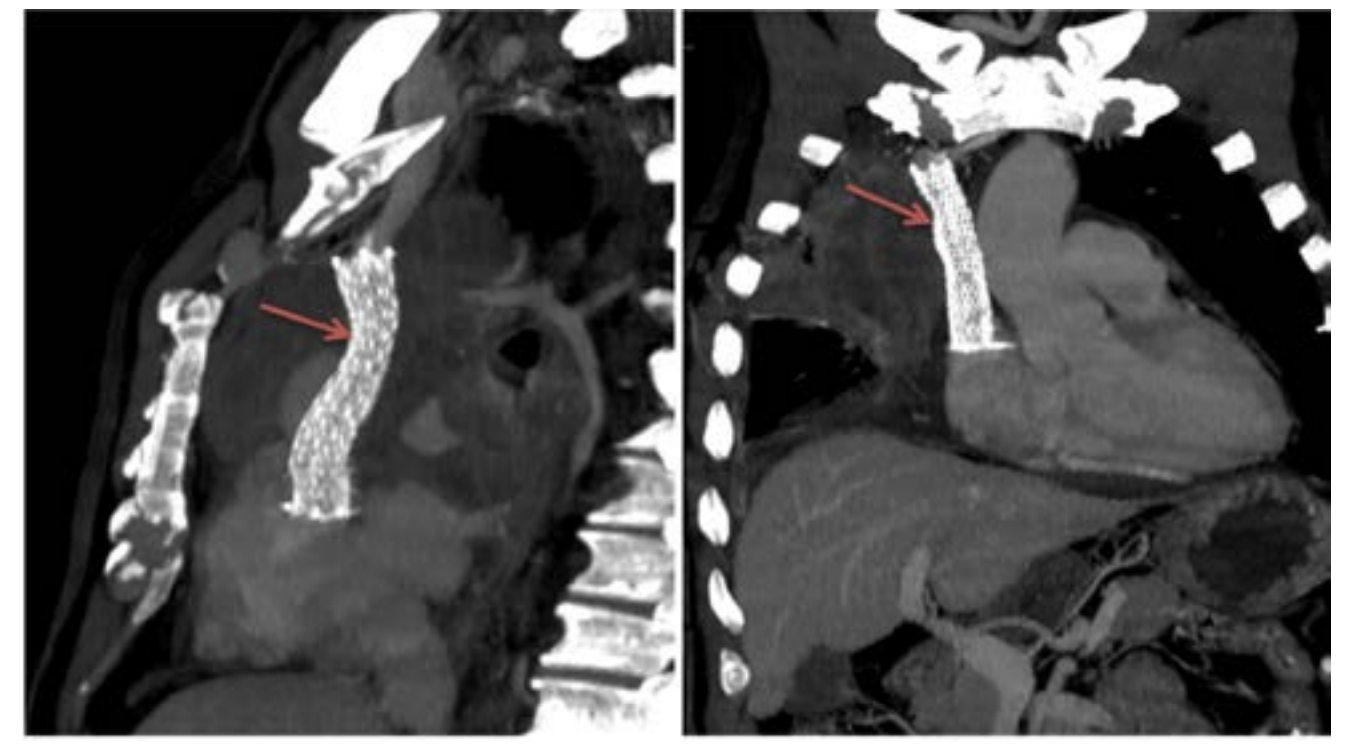

The caval stenosis, in the series, was diagnosed by means of an angio CT scan of the chest, followed by confirmation using the venacavogram.

From a therapeutic point of view, endovascular treatment of SVCS had been performed under local anesthesia. Percutaneous vena femoral approach was carried out in 2 cases. Three patients also required the use of the basilica pathway. Before stenting, the caval stenosis was dilated two or three times for almost 10 minutes by means of balloon inflation to the estimated diameter in three cases. We also routinely performed post-stent dilatation. In all procedures, a self-expanding stent had been deployed. The details regarding the stent deployed are summarized in Table 1. As an immediate follow-up, the patients experienced a quick relief of symptoms between 48-72 hours.

In what concerns the place of imaging exploration, the majority of authors believe that CT-scan with its high-quality multiplanar reconstructions is a crucial imaging tool. In fact, angio-CT scan confirms the diagnosis, determines the exact extent of obstruction, the nature and the degree of vena cava obstruction as well as it orients the placement of the endoprosthesis and the presence of associated pathologies.6 A venographic classification according to Stanford and Doty was set. Four Patterns of venous collateral return have been described.5 The 4th one matches with the most severe in terms of clinical symptoms (Schema 1).